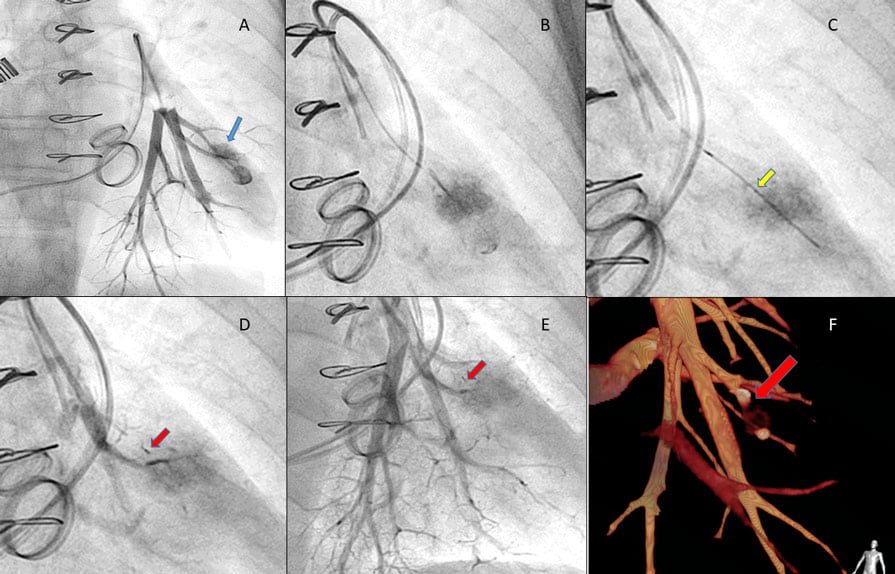

With the thermodilution catheter inflated in the pulmonary artery, an angiogram was performed. It demonstrated the formation of a pseudoaneurysm with extravasation of contrast. The tip of the catheter was inserted in the left pulmonary branch and the balloon was inflated to half its prior volume, creating a tamponade effect and stopping the hemoptysis (Figure 1A, Moving image 1).

Figure 1: Repair of iatrogenic perforation of a pulmonary artery side branch with Micro Vascular Plug System

The balloon was inflated for ten minutes, with periodic deflations, and angiograms were performed through the distal port of the catheter to determine if the rupture would seal, with no success.

At the same time, another vascular access was obtained by the left femoral vein. A multipurpose 6 F catheter was advanced to the damaged branch, and a Terumo Progreat® 2.7 Fr microcatheter was inserted (Figure 1B, Moving images 2,3).

MVP™ Micro Vascular Plug System® Q5 (Medtronic) for peripheral embolization was deployed (Figure 1C) with completed and immediate mechanical occlusion (Figures 1 D, E, red arrow, Moving image 4).

The final angiography demonstrated resolution and clotting of the affected pulmonary artery pseudoaneurysm. The adjacent pulmonary artery remained free from injury.

A computed tomography scan performed 3 days later demonstrated no acute bleeding, a small hematoma in the left inferior pulmonary lobe, with the perforation completely sealed (Figure 1F).